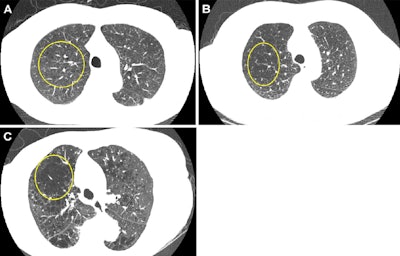

Representative axial images of mild, moderate, and severe emphysema at baseline low-dose CT (LDCT). Participants were categorized as having no emphysema or mild, moderate, or severe emphysema. When present, emphysema was mild if no distinct regions of reduced attenuation were visible on the CT scan, but vascular splaying indicates parenchymal expansion, or if only occasional discrete low-attenuation regions were observed. Moderate emphysema was defined by the presence of identifiable low-attenuation regions affecting less than half of the lung parenchyma, whereas severe emphysema was defined by the presence of identifiable low-attenuation regions that involved more than half of the lung parenchyma. A scoring system from 0 to 3 was applied, corresponding to none, mild, moderate, and severe emphysema, respectively. Yellow circle indicates the extent of emphysema. (A) A 67-year-old man with mild emphysema at baseline LDCT in 2002. Baseline LDCT scan shows vascular splaying, suggesting parenchymal expansion due to emphysema and occasional discrete low-attenuation regions. The participant ultimately died of cardiovascular disease 15.4 years (184.2 months) later. (B) A 69-year-old man with moderate emphysema at baseline LDCT in 2007. The participant died of cardiovascular disease 1.8 years (21.9 months) later. Identifiable low-attenuation regions affected less than half of the lung parenchyma. (C) An 85-year-old woman with severe emphysema at baseline LDCT in 2006. After 5.5 years (65.5 months) of follow-up, the participant died due to chronic obstructive pulmonary disease–related causes. Identifiable low-attenuation regions involved more than half of the lung parenchyma.Representative axial images of mild, moderate, and severe emphysema at baseline low-dose CT (LDCT). Participants were categorized as having no emphysema or mild, moderate, or severe emphysema. When present, emphysema was mild if no distinct regions of reduced attenuation were visible on the CT scan, but vascular splaying indicates parenchymal expansion, or if only occasional discrete low-attenuation regions were observed. Moderate emphysema was defined by the presence of identifiable low-attenuation regions affecting less than half of the lung parenchyma, whereas severe emphysema was defined by the presence of identifiable low-attenuation regions that involved more than half of the lung parenchyma. A scoring system from 0 to 3 was applied, corresponding to none, mild, moderate, and severe emphysema, respectively. Yellow circle indicates the extent of emphysema. (A) A 67-year-old man with mild emphysema at baseline LDCT in 2002. Baseline LDCT scan shows vascular splaying, suggesting parenchymal expansion due to emphysema and occasional discrete low-attenuation regions. The participant ultimately died of cardiovascular disease 15.4 years (184.2 months) later. (B) A 69-year-old man with moderate emphysema at baseline LDCT in 2007. The participant died of cardiovascular disease 1.8 years (21.9 months) later. Identifiable low-attenuation regions affected less than half of the lung parenchyma. (C) An 85-year-old woman with severe emphysema at baseline LDCT in 2006. After 5.5 years (65.5 months) of follow-up, the participant died due to chronic obstructive pulmonary disease–related causes. Identifiable low-attenuation regions involved more than half of the lung parenchyma.Image and caption courtesy of the RSNA.